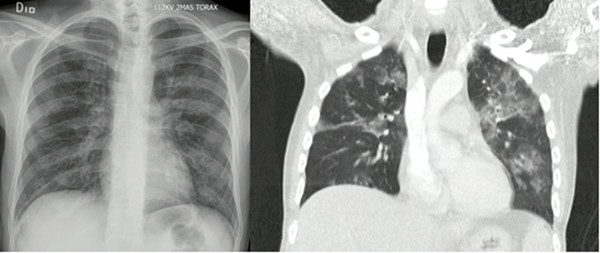

Los principales hallazgos radiológicos descritos son infiltrados intersticiales, nódulos, neumatoceles, cambios quísticos y neumotórax (23). En la tomografía axial computarizada se puede observar patrón en vidrio esmerilado con distribución en parches o con opacidades difusas bilaterales (figura 1) (20). El patrón de oro es la demostración directa del microrganismo, bien sea en esputo, lavado broncoalveolar (LBA) o biopsia pulmonar. El LBA establece el diagnóstico en el 90 % de los casos y el porcentaje de neutrófilos en la muestra se considera un predictor de mortalidad a 90 días (8). Otros métodos diagnósticos incluyen anticuerpos monoclonales para P. jirovecii y reacción en cadena de la polimerasa; sin embargo, el rendimiento de estas pruebas no supera el de los métodos convencionales (20).

En otro estudio descriptivo realizado por Cañas y cols (8), en Bogotá, entre 2005 y 2010, se reportó como síntoma principal de la infección por Pneumocystis jirovecii la fiebre (80 %); adicionalmente, se describió como hallazgo más frecuente en la radiografía de tórax los infiltrados intersticiales (61,9 %), seguido por los infiltrados alveolares difusos (42,8 %). Entre tanto, en la tomografía axial computarizada de alta resolución (TACAR) el principal hallazgo obtenido fue la presencia de patrón en vidrio esmerilado en el 92,3 % de los pacientes.